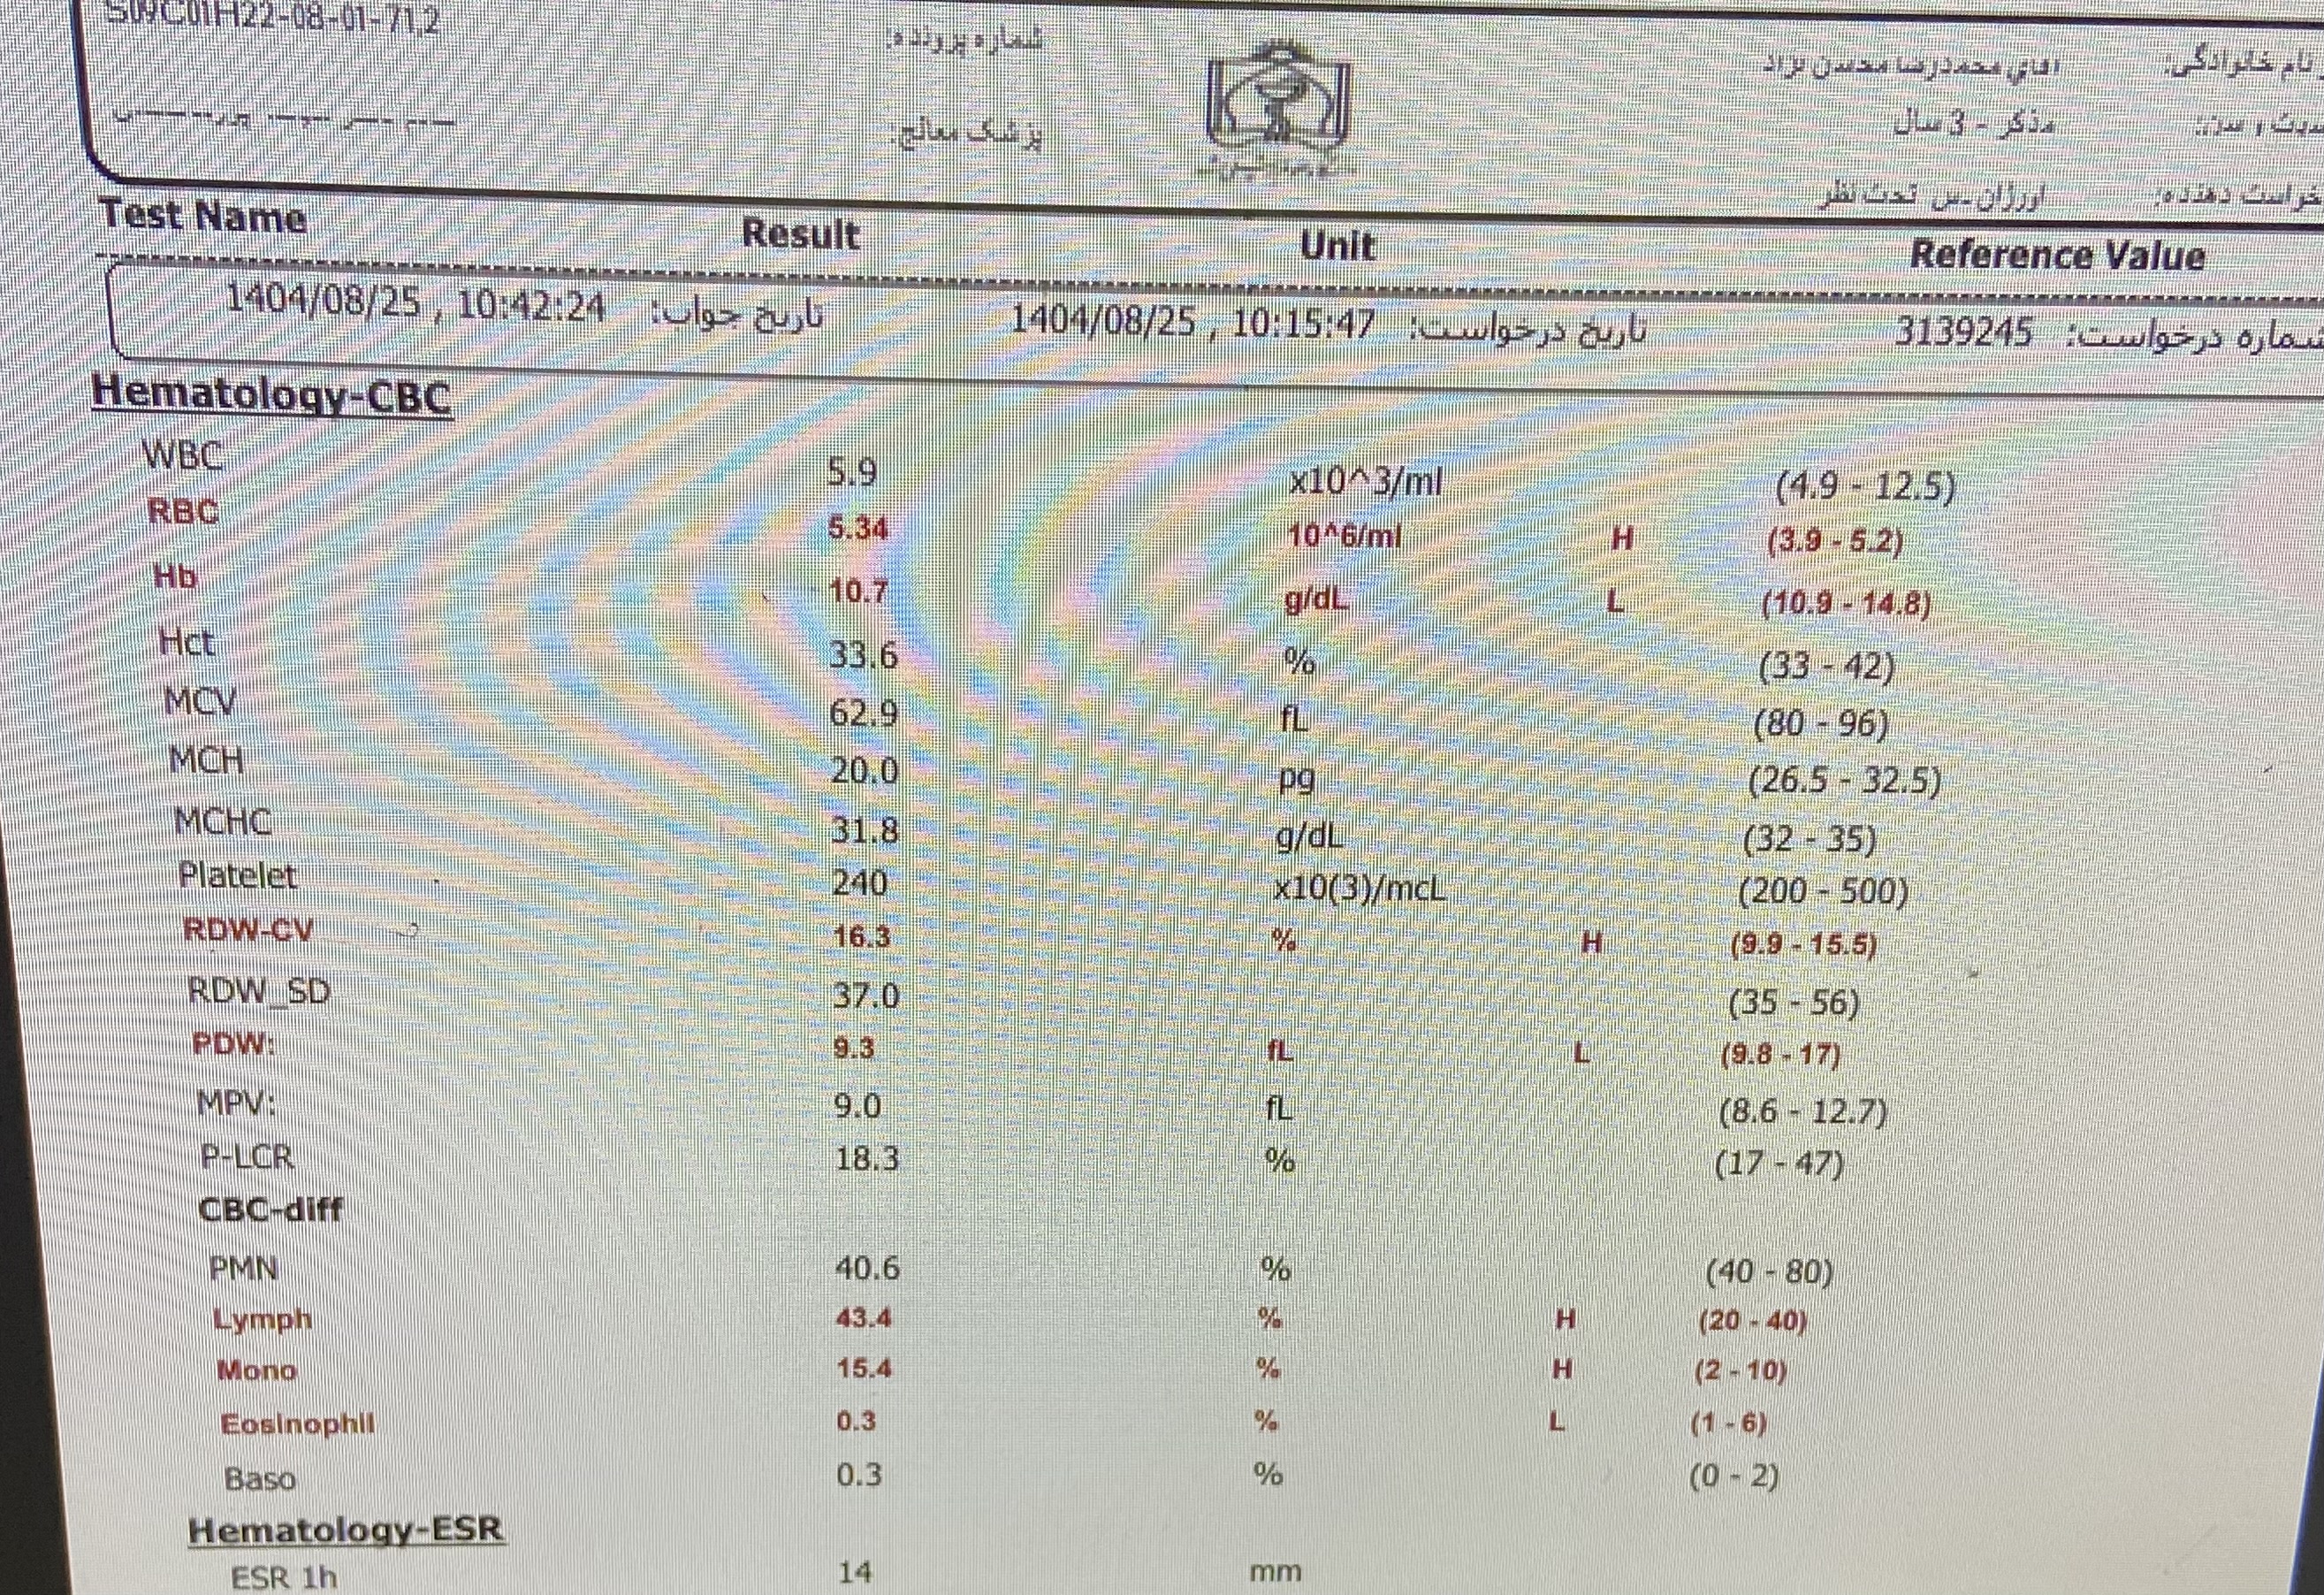

بیمار پسر ۲ سال ونه ماه مورد cah از ۱۷ روزگی تشخیص شده (با علایم اولیه poor feeding و تیرگی پنیس و لب وپتاسیم ۹ )با سرفه prوتب از دیشب شروع شده به اورژانس مراجعه کرده وهمچنین ۳ نوبت استفراغ داشته وابریزش بینی وسایقه بستری مکرر داشته با شک به گریز ادرنال بستری شدن

پسر 2ساله ونه ماه با تب وسرفه وابریزش و۳ بار استفراغ از دیشب به اورژانس مراجعه کرده مورد cah از ۱۷ روزگی تحت درمان با هیدروکورتیزون و فلودروکورتیزون بوده با شک به کریز ادرنال بستری شدن تاکی پنه وتاکی کاردی داشته

برای این کیس هنوز آزمایشی ثبت نشده است.